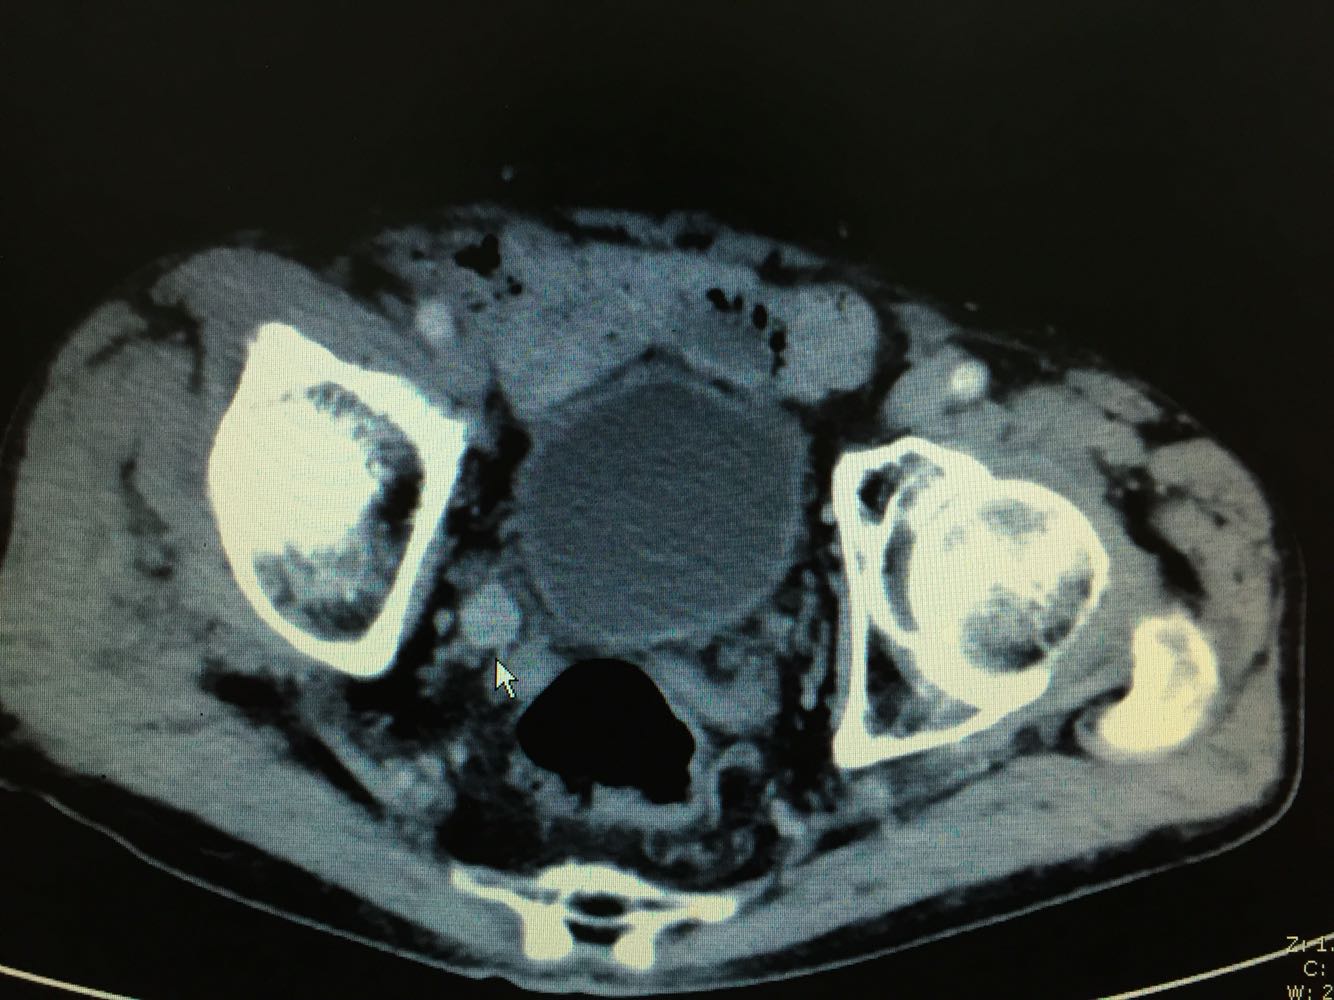

右肾区叩痛阳性。 CTU提示右侧输尿管下段肿瘤,右肾积水。 尿脱落细胞提示,查见癌细胞。

右侧输尿管下段癌,行后腹腔镜下右侧输尿管癌根治性切除术